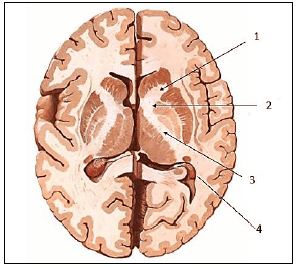

Cada hemisfério possui uma camada superficial de substância cinzenta, o córtex cerebral, que reveste um centro de substância branca – o centro medular do cérebro ou centro semioval. No interior dessa substância branca, há massas de substância cinzenta – os núcleos da base do cérebro. O centro branco medular do cérebro é formado por fibras mielínicas, que podem ser de dois tipos – de projeção ou de associação. As fibras de projeção se dispõem em dois feixes – o fórnix e a cápsula interna.

Assinale, a seguir, o número correspondente ao joelho da cápsula interna na imagem.

Provas